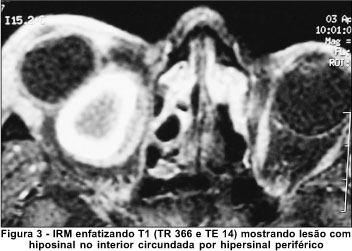

À imagem por ressonância magnética revelou lesão bem delimitada com sinal que nos cortes evidenciando T1 (TR 366 e TE 14) apresentava hiposinal no interior circundado por hipersinal periférico (Figura 3). Nos cortes evidenciando T2 (TR 5150 e TE 85,2) a lesão apresentava-se quase que totalmente hiperintensa, apenas com pequeno halo periférico de hiposinal (Figura 4). Tais achados eram compatíveis com uma lesão contendo sangue recente na periferia e produtos de degradação do sangue (metahemoglobina) indicativos da presença também de sangramento subagudo dentro da lesão.

Esta características são distintas dos achados à IRM obtidos nas outras lesões císticas acima mencionadas, com as quais o cisto hemático faz diagnóstico diferencial. Isto ocorre uma vez que o cisto hemático usualmente apresenta hemorragias em diferentes fases, uma vez que é comum o resangramento dentro da lesão. Hemorragias agudas demonstram sinal intermediário em T1 e muito diminuído em T2, como pode ser observado na periferia da lesão em nosso paciente (Figuras 3 e 4). Hemorragias na fase subaguda mostram hipersinal periférico tanto em T1 como em T2 devido ao acúmulo periférico de metahemoglobina (Figuras 3 e 4). Na fase crônica, todo o hematoma mostra sinal de alta intensidade(9-10). Nosso paciente apresentava, portanto, hematoma com características agudas (na periferia) e subagudas (na sua maior parte). Tais achados são muito distintos de outras lesões tumorais acima mencionadas, incluindo o cisto hidático da órbita, que geralmente mostram sinal baixo em T1 e alto em T2 e com as quais o cisto hemático faz diagnóstico diferencial(9,11).